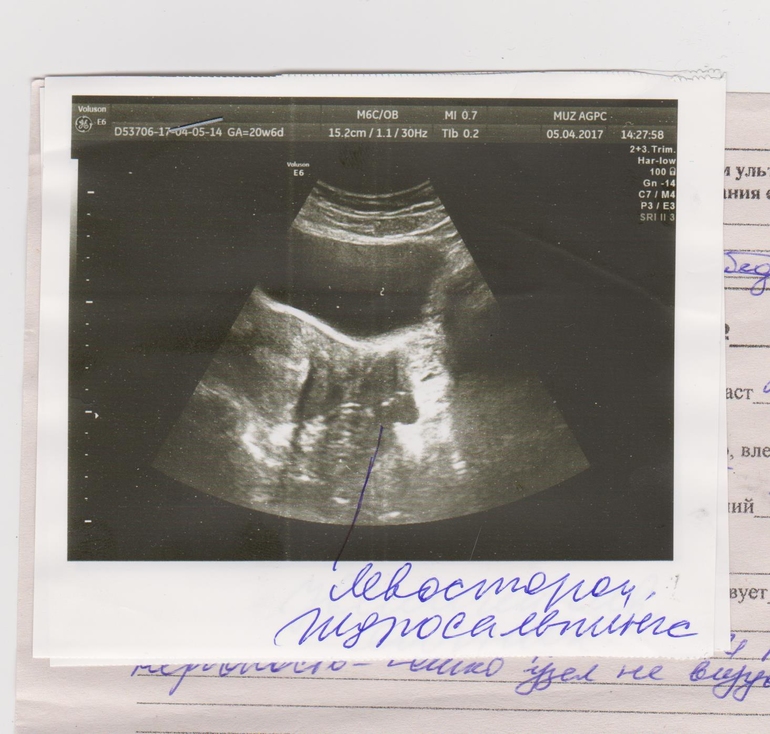

Ждем дня Х (Признаки беременности / Тесты)Девочки я уже писала ранее про начало цикла,про три узи на которых были поставлены разные диагнозы и которые не подтверждались.Так вот после овуляции которая примерно была 14-15 дц начались тянущие ощущения в низу живота и поясницы,иногда сверлящие кратковременные боли,так же чуть ли не каждый день тошнота будь она не ладна(((И девочки у меня последние пол года после О и до М мучали болючие прыщи на спине,а тут их просто нет,уфффф как здорово ИХ НЕТ!!!! Но вот эта тянущесть в низу живота и пояснице покоя не даёт до сих пор покоя ни днём ни ночью.из за этого не могу уснуть и потом всю ночь ворочаюсь.Пошла позавчера в больницу,отправили опять на узи,и о боже у меня нашли гидросальпинкс и опять яичник увеличен вдвое(((фото предпоследнего,последнего и вчерашнего узи прилагаю.Тесты делала на 8 и 9 дпо примерно и в это же время делала тесты на О,не кидайтесь тапками мне просто было интересно.Тесты на Б вроде пустые,но я видела призраков.На О были сначало поярче потом потускнели,а тут вроде опять начали набирать яркость,а сегодня полоска жирнючая но не очень яркая,хотя все из одной коробки и на всех тонюсенькие.Тест на Б последние два дня не делала.Девочки может врачи ошибаются по поводу этих болячек?У меня есть шанс на беременность?